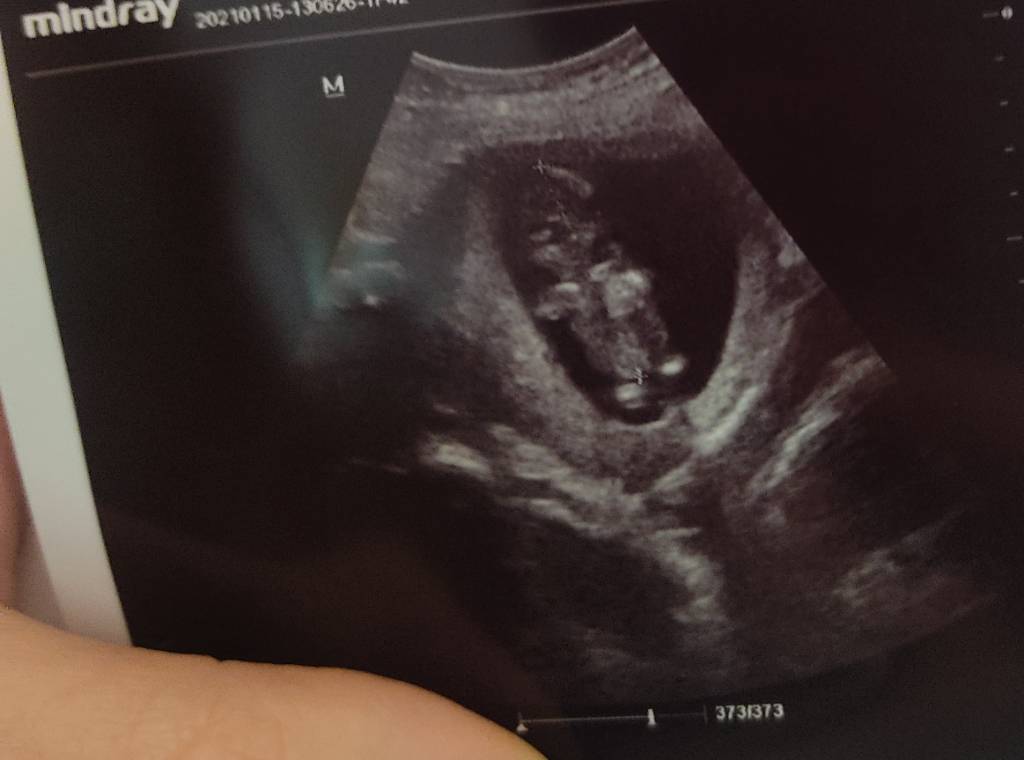

Jestem po wizycie. Widziałam maluszka. Wszystko w porządku. Wg USG 12tydzien, wg terminu z okresu 12+4 także zobaczymy kiedy się wykluje. Maluszek był bardzo spokojny,chyba spał ;)

• IMG_20210115_124837.jpeg

IMG_20210115_124837.jpeg

42,8 KB · Wyświetleń: 98